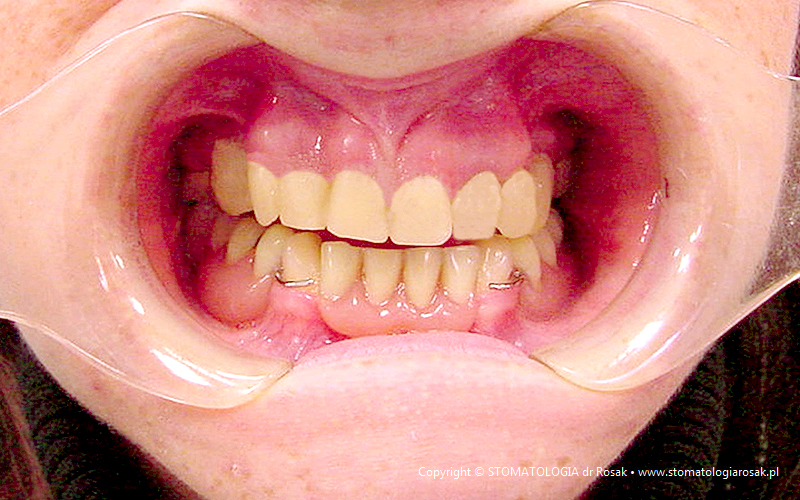

9. Pacjent lat 57- zgłosił się celem usunięcia zniszczonych zębów i wykonania protez ruchomych całkowitych.

NIE USUNĘLIŚMY - ANI JEDNEGO ZĘBA!!!

| 9a. Przed leczeniem |

9b. Gotowe korony i mosty porcelanowe na górze

(trójkę górną prawą pacjent zażyczył sobie nie korygować)

oraz w żuchwie tzw. czapeczki pokrywające oraz zatrzaski kulowe dla lepszego utrzymania protezy ruchomej dolnej |

| 9c. Gotowa praca |